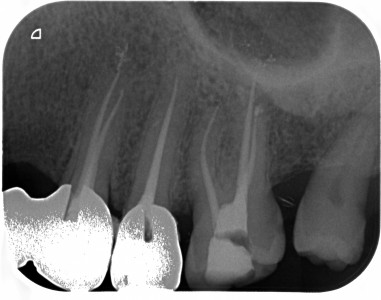

Devitalizzazione

Caso eseguito dal

Dr. Luca Schiavio